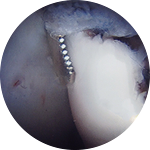

Hip arthroscopy can trim out the unstable cartilage, or in some cases perform a microfracture of the bone to stimulate the growth of new cartilage.